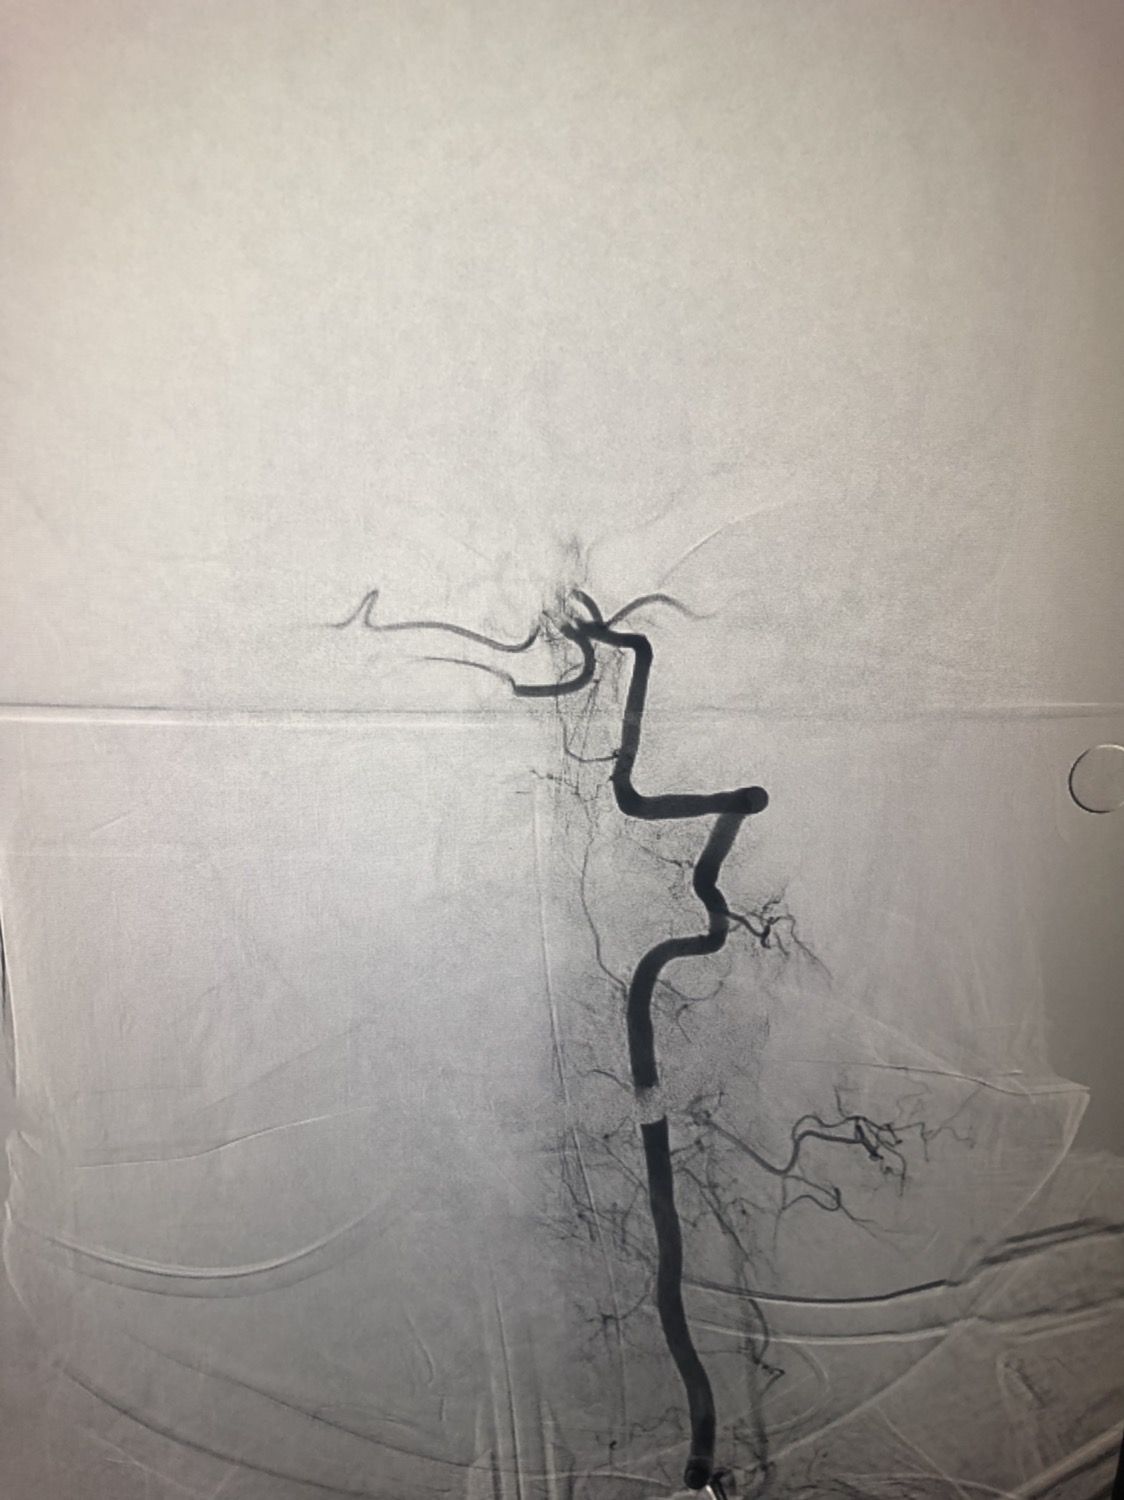

1周前房颤栓塞肱动脉,切开取栓后服用利伐沙班3天。突发偏瘫凝视3小时。上台看M3、A3血栓,国产普威森6f125cm抽吸导管高到位结合尼科3x20mm小支架,结合精细操作,m3和a3的血栓也可以轻松取出。不刺激血管。加造影射线16min两次取栓两个血管再通。

柔软的国产普威森微导管,高到位。

3x20mm的国产reco支架,适合分支血管取栓。